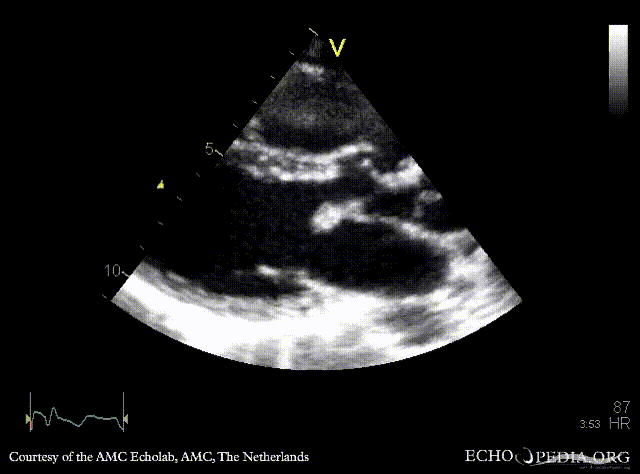

| Courtesy of: AMC Echolab, AMC, The Netherlands | |

| PLAX | PLAX: Color Doppler, ????? |